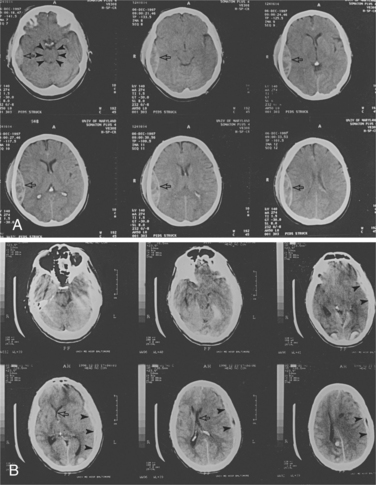

Vascular Changes.: Focal brain injuries usually result in cerebral contusions. Vascular damage is sustained at the moment of impact and leads to infarction within the cortical grey matter. Glial elements encapsulate the infarction, ultimately creating a residual cystic cavity.26 Typically, contusions occur at the poles and on the inferior surfaces of the frontal and temporal lobes. Occipital blows are more likely to produce contusions than are frontal or lateral blows. Areas where the cranial vault is irregular, such as on the anterior poles, undersurface of the temporal lobes, and undersurface of the frontal lobes are commonly injured. With fracture of the cranial vault, there may be damage to the superficial epidural vessels and, particularly in the case of falls, there can be rupture of the bridging vessels between hemispheres.42 Fig. 33-3 shows CT scan images of changes seen after TBI.

Figure 33-3 CT scans of two patients with closed head injury. A, This patient has a right temporal epidural hematoma (arrows). The mesencephalic cisterns are patent in the top left, indicating a lack of brainstem compression despite mass (arrowheads). B, This patient has suffered an acute left subdural hematoma (arrowheads) with midline shift (arrows). (Reprinted from Townsend CM: Sabiston textbook of surgery, ed 17, Philadelphia, 2004, Saunders.)

TBI can be associated with other forms of vascular change. Gliding contusions, or hemorrhagic lesions in the cortex, may be the result of movement of the cortical grey matter in relation to the underlying white matter, causing shear strains to damage the penetrating vessels found at the grey and white matter interface.57 Fig. 33-4 shows the effects of shearing injury as seen on CT scan. Subarachnoid hemorrhage is common due to the rupture of pial vessels within the subarachnoid space. This may trigger vasospasm that can lead to reduced regional blood flow. Injury to the vessels within the white matter can also cause significant neurologic consequences, especially if it is in the area of the basal ganglia.26

Figure 33-4 Contusion with shearing injury. CT scan shows multiple rounded areas of blood density with surrounding edema. Many of these areas are at the junction of grey and white matter consistent with shear injury. (Reprinted from Ramsey R: Neuroradiology, Philadelphia, 1994, WB Saunders, p 409.)